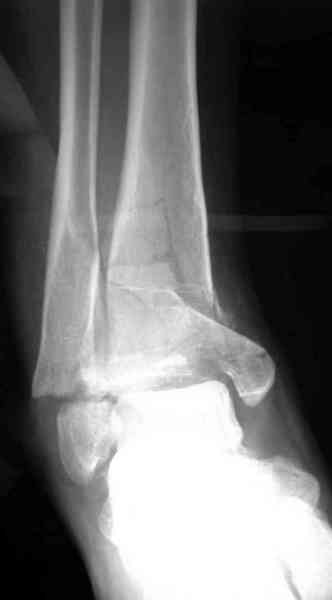

Добавлены КТ снимки. Прошу прощения за качество.

С уважением, Коваленко А.Н.